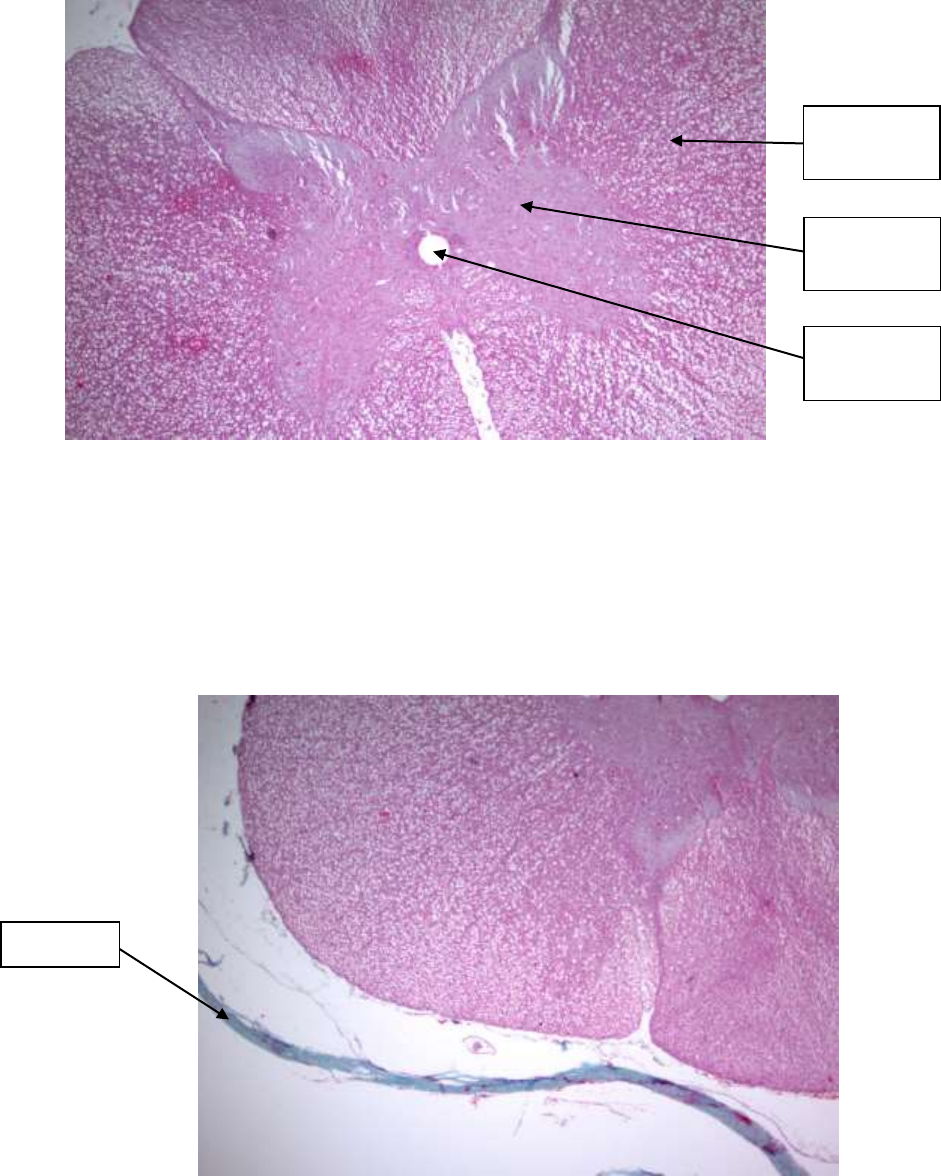

Lâmina - Corte de medula espinhal e gânglio

Coloração: Tricrômico de Gomori

Medula espinhal (40X)

Observe, na medula, uma área de coloração mais clara. Esta área corresponde à

substância branca. Além dela, existe uma região mais escura, central, com a forma de

H, que corresponde à substância cinzenta.

Note que a substância cinzenta apresenta 2 cornos anteriores (mais globosos) e dois

posteriores, de tamanho menor.

Substância

branca

cinzenta

Canal

medular

Pia-máter

Colado ao tecido nervoso, na sua periferia, está um tecido conjuntivo, corado em verde.

É a pia-mater. Daí partem septos, com vasos sanguíneos, que penetram na medula até

uma certa distância.